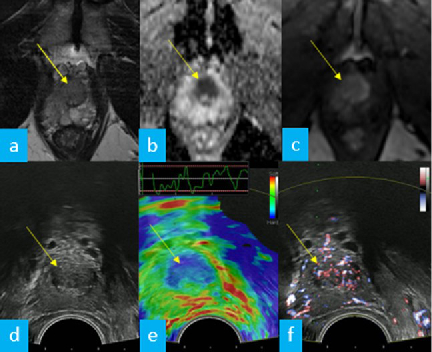

The simultaneous application of structural and functional imaging techniques is described as multiparametric (MP) (Fig. 9). Studies have shown that the MP approach results in greater diagnostic accuracy (Fig. 10).

The use of fusion imaging in uroradiology improves ultrasound lesion-detection rates, shows more reliable size controls at different time points, is an alternative to in-bore biopsies (Fig. 11) and can be used for focal therapy.